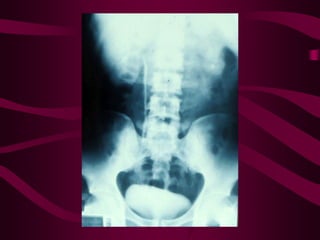

Este documento describe la tuberculosis genitourinaria. Afecta más a hombres que a mujeres. Se transmite principalmente a través de la infección pulmonar primaria y luego se disemina a través de la sangre a los riñones u otros órganos. Causa lesiones como granulomas y necrosis si no se controla, lo que puede provocar complicaciones como abscesos e insuficiencia renal. Se diagnostica mediante pruebas de orina y tratamiento con medicamentos durante varios meses.